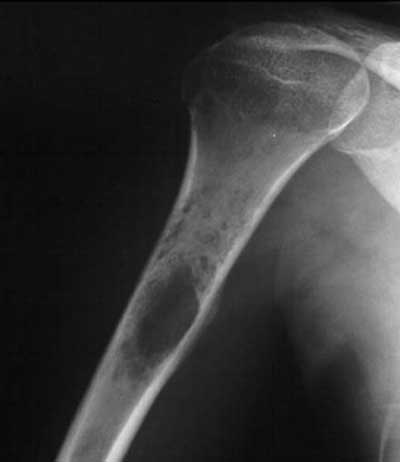

استئوسارکوم بیشتر در افراد کم سن و سال ایجاد می شود و به سرعت به قسمت های دیگر بدن نفوذ می کند. محل تشکیل این تومور نیز در بالا و پایین زانوها و شانه ها به خصوص در استخوان های بلند این نواحی است. قابل ذکر است که این تومور در صفحات رشد استخوان های ناحیه های ذکر شده ایجاد می شود.